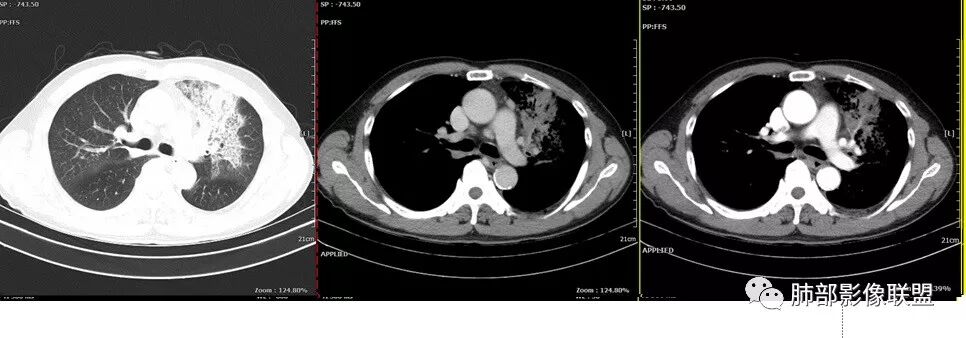

这个是9月7号的平扫CT

右下肺病理没有报癌

但是化疗2次后也缩小了

背段入口在CT上也可以见到了

回头看尖段的分支和背段肯定是堵了,两处应该都是鳞癌,右肺基底段的就不知道了。

复查的HRCT

化疗2次。

应该是阻塞性肺炎,抗感染后查PET CT的时候左上肺已经有部分吸收了。

前段堵了

右下背还是考虑恶性可能

支气管镜下明显见到新生物了,病理取到表面粘膜。

鳞癌起源于支气管粘膜,是气道中最常见的恶性肿瘤,易造成支管壁增厚,并突入腔内形成结节,造成狭窄、阻塞或截断;早期鳞癌表现为沿支气管生长的梭形结节或局限性增厚,辖区内常出现阻塞性炎症,这样的病灶赢多平面重建并仔细观察支气管改变;如果有支气管壁偏心性增厚伴管腔狭窄或腔内结节形成,都要想到早期鳞癌的可能性,复查或内窥镜检查是必要的。

鳞癌好发于中老年人,与吸烟关系密切,如果发现不易吸收的,或同一部位反复无常局限性肺炎,我们应当仔细观察支气管壁的病变除外阻塞的可能;该病例右肺下叶背段及左肺上叶支气管有肿块及管壁的增厚,应当想到恶性可能。

1.右肺下叶支气管壁增厚,后壁为主,且显示壁外结节,未见异常强化。这样的结节和蔓延方式一般会高度怀疑气道来源的恶性肿瘤,如鳞癌、粘液表皮样癌、腺样囊性癌等。可惜没有相应病理学资料支持。

右肺下叶近膈面球形病灶缺乏恶性病灶特点,没有分叶、毛刺、牵拉等,应当符合炎性。

2.左肺上叶大范围高密度影,几乎占据整个肺叶,没有体积改变,尽管小叶间隔显示明显,但初诊还是首先会想到社区肺炎,尤其是结合患者有发热及左侧胸痛的临床表现。

会是粘液腺癌吗?如此大范围,又在上叶,周围却未见向外飘散的结节影,难以想象。

3.我们都注意到患者左肺上叶支气管开口的改变,这种改变有可能会用常见的“肉芽肿性炎”或“分泌物”加以解释,因管腔内的隆起部分未能观察到强化,管壁外未见相应快影或结节影。

熟料问题恰恰出在这里!它没能引起完全阻塞,未能形成“S”形肺不张。

该病例非常值得我们警醒,忽略支气管管腔内的任何异常都可能大意失荆州!